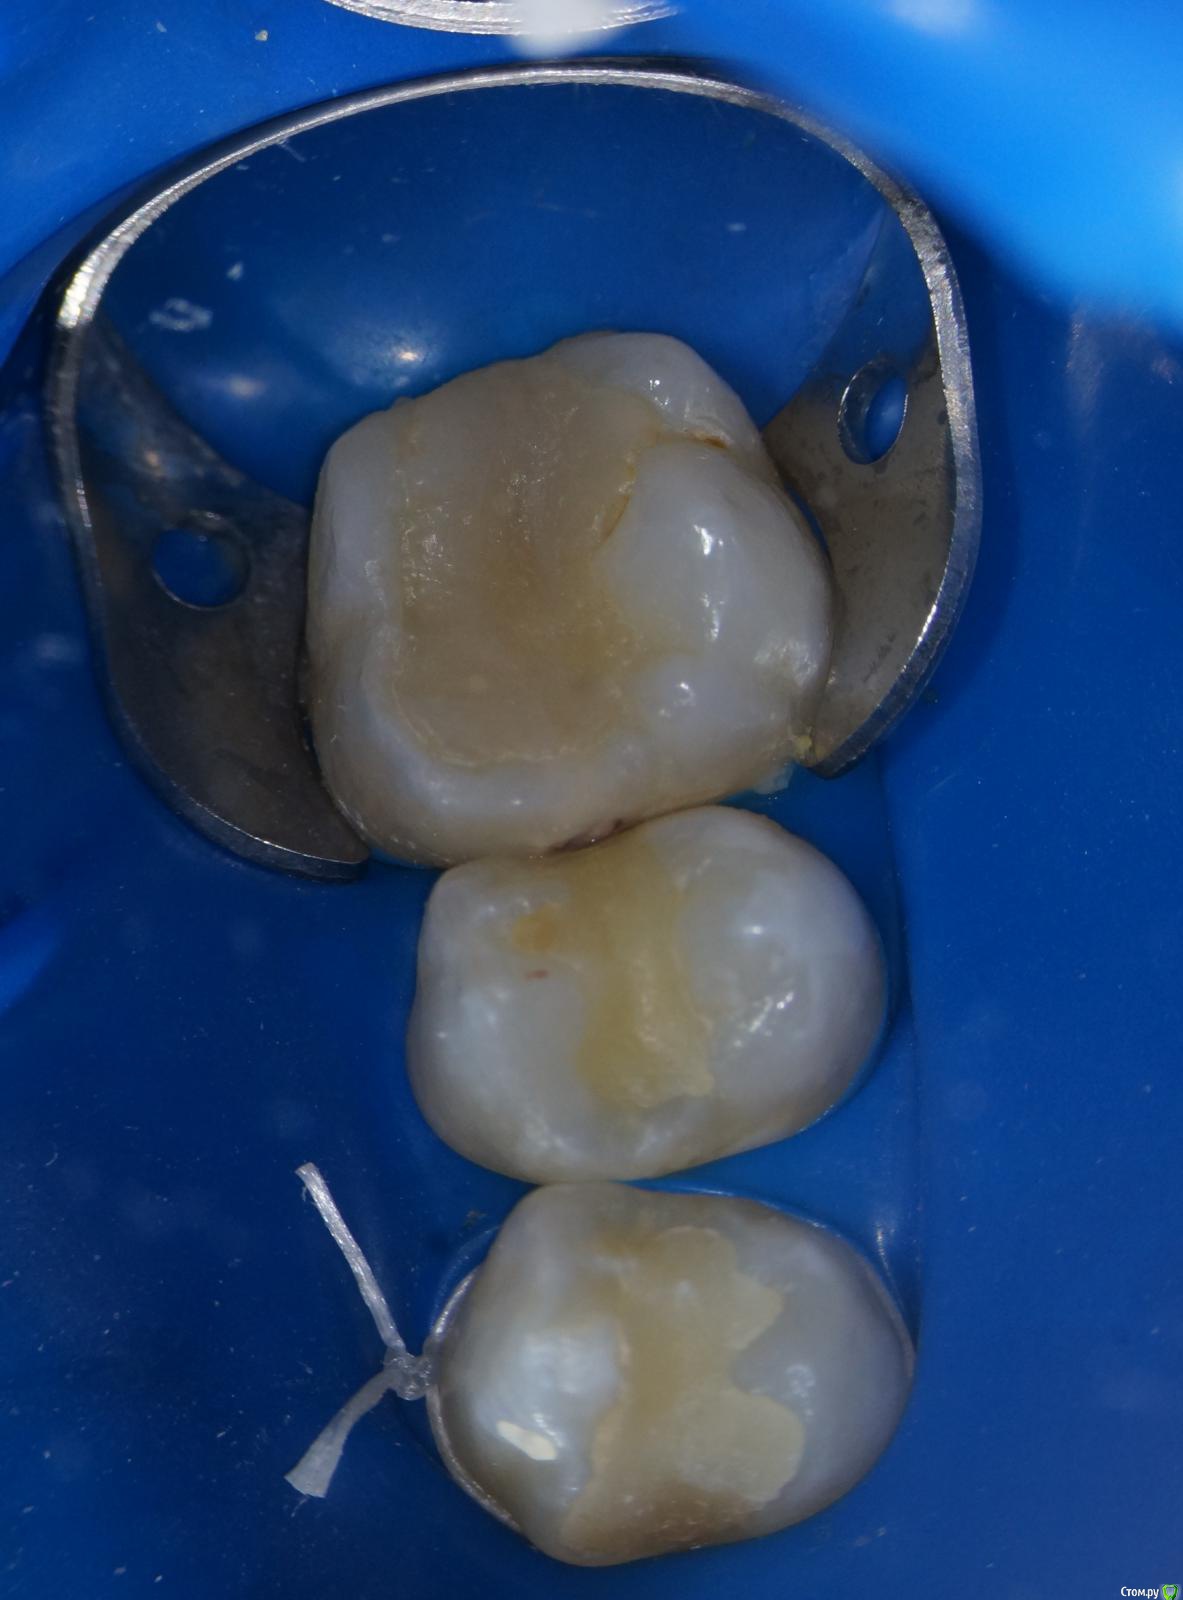

Hans85 Опубликовано 15 января, 2014 Автор Поделиться Опубликовано 15 января, 2014 Сразу скажу что с эндо у меня обстоит лучше чем с реставрациями так что сильно не пинайте.Пациентка страховая,так что речь про вкладки не идет.так сказать возможность тренится в художественной лепке.ЗУбы 26 25 24.На фото 26 уже сделанный. 7 Ссылка на комментарий